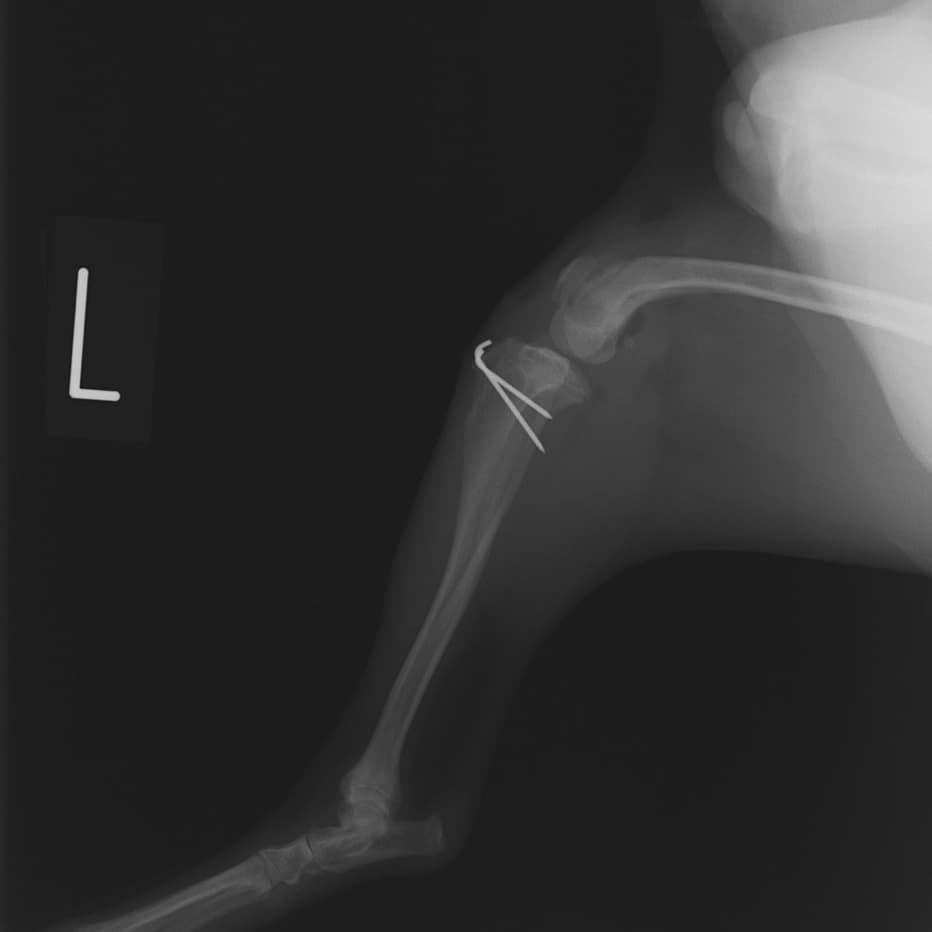

■ 症例20 ポメラニアン 8ヶ月 1.8kg

左右膝蓋骨脱臼 グレードⅢ

2ヶ月前から間欠的跛行が認められ、両膝の膝蓋骨脱臼整復術を行った。

手技は縫工筋及び内側広筋の解放、脛骨粗面の外側転位、滑車ブロック形造溝術、内外側関節包の縫縮を選択し実施した。

右側の膝蓋骨脱臼は上記手技で整復されたものの、左側はそれのみでは膝蓋骨が浮く様子が認められた。その為、PDS縫合糸にて膝蓋靱帯を1糸のみ縫合し、靱帯の縫縮を行った。

膝蓋骨脱臼は膝関節における膝蓋骨の内外側の脱臼と定義されるが、時として単純な内外の脱臼ではなく、膝蓋骨が大きく前方に浮き上がるように脱臼する場合がある。特にトイプードルやポメラニアンといった犬種に多く認められる。

内側脱臼に加えて前方への浮き上がりを矯正する為に、従来より脛骨粗面転移により膝蓋靭帯を外方と下方に引っ張り、固定する方法を選択する。膝蓋骨の前方への浮き上がりが軽度の場合は、従来法ではなく関節包の縫縮で対応していた。しかし、一部の症例で膝蓋骨の動きが悪くなり伸展機構が円滑に機能せずロボット様歩行になるケースがあった。

その為、膝蓋靭帯自体を縫縮する方法を採用した。この方法により、膝関節の伸展機構を妨げず膝蓋骨の軽度の浮きを矯正することが可能となった。

本症例の経過は良好である